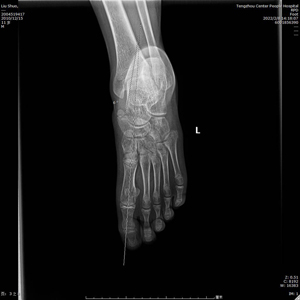

術(shù)前X線示:左足平足并副舟骨?;颊呓?jīng)過足跟墊等保守治療效果不佳,潘維亮主任醫(yī)師主持全科醫(yī)護人員術(shù)前討論一致決定為患者實施全麻下距下關(guān)節(jié)制動術(shù)。

(術(shù)后X線)